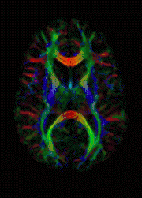

擴散磁振造影

1980年代中期擴散核磁造影的理論已被提出,1986年 Le Bihan 提出擴散磁振造影臨床應用的潛在可能性。1990年Moseley的論文提到偵測貓的大腦局部缺血情況。1994年Basser推導出擴散張量磁振造影(Diffusion Tensor Imaging, DTI)的理論,2000年Wedeen成功發展擴散譜影像的技術。擴散核磁造影結合了PGSE測量擴散磁振訊號與擴散磁振造影技術的概念,可應用於早期診斷缺血性腦中風,可以準確評估腦部、肝臟腫瘤的治療效果。

擴散核磁造影,全名水分子擴散核磁造影,是一種更進步的核磁共振技術。